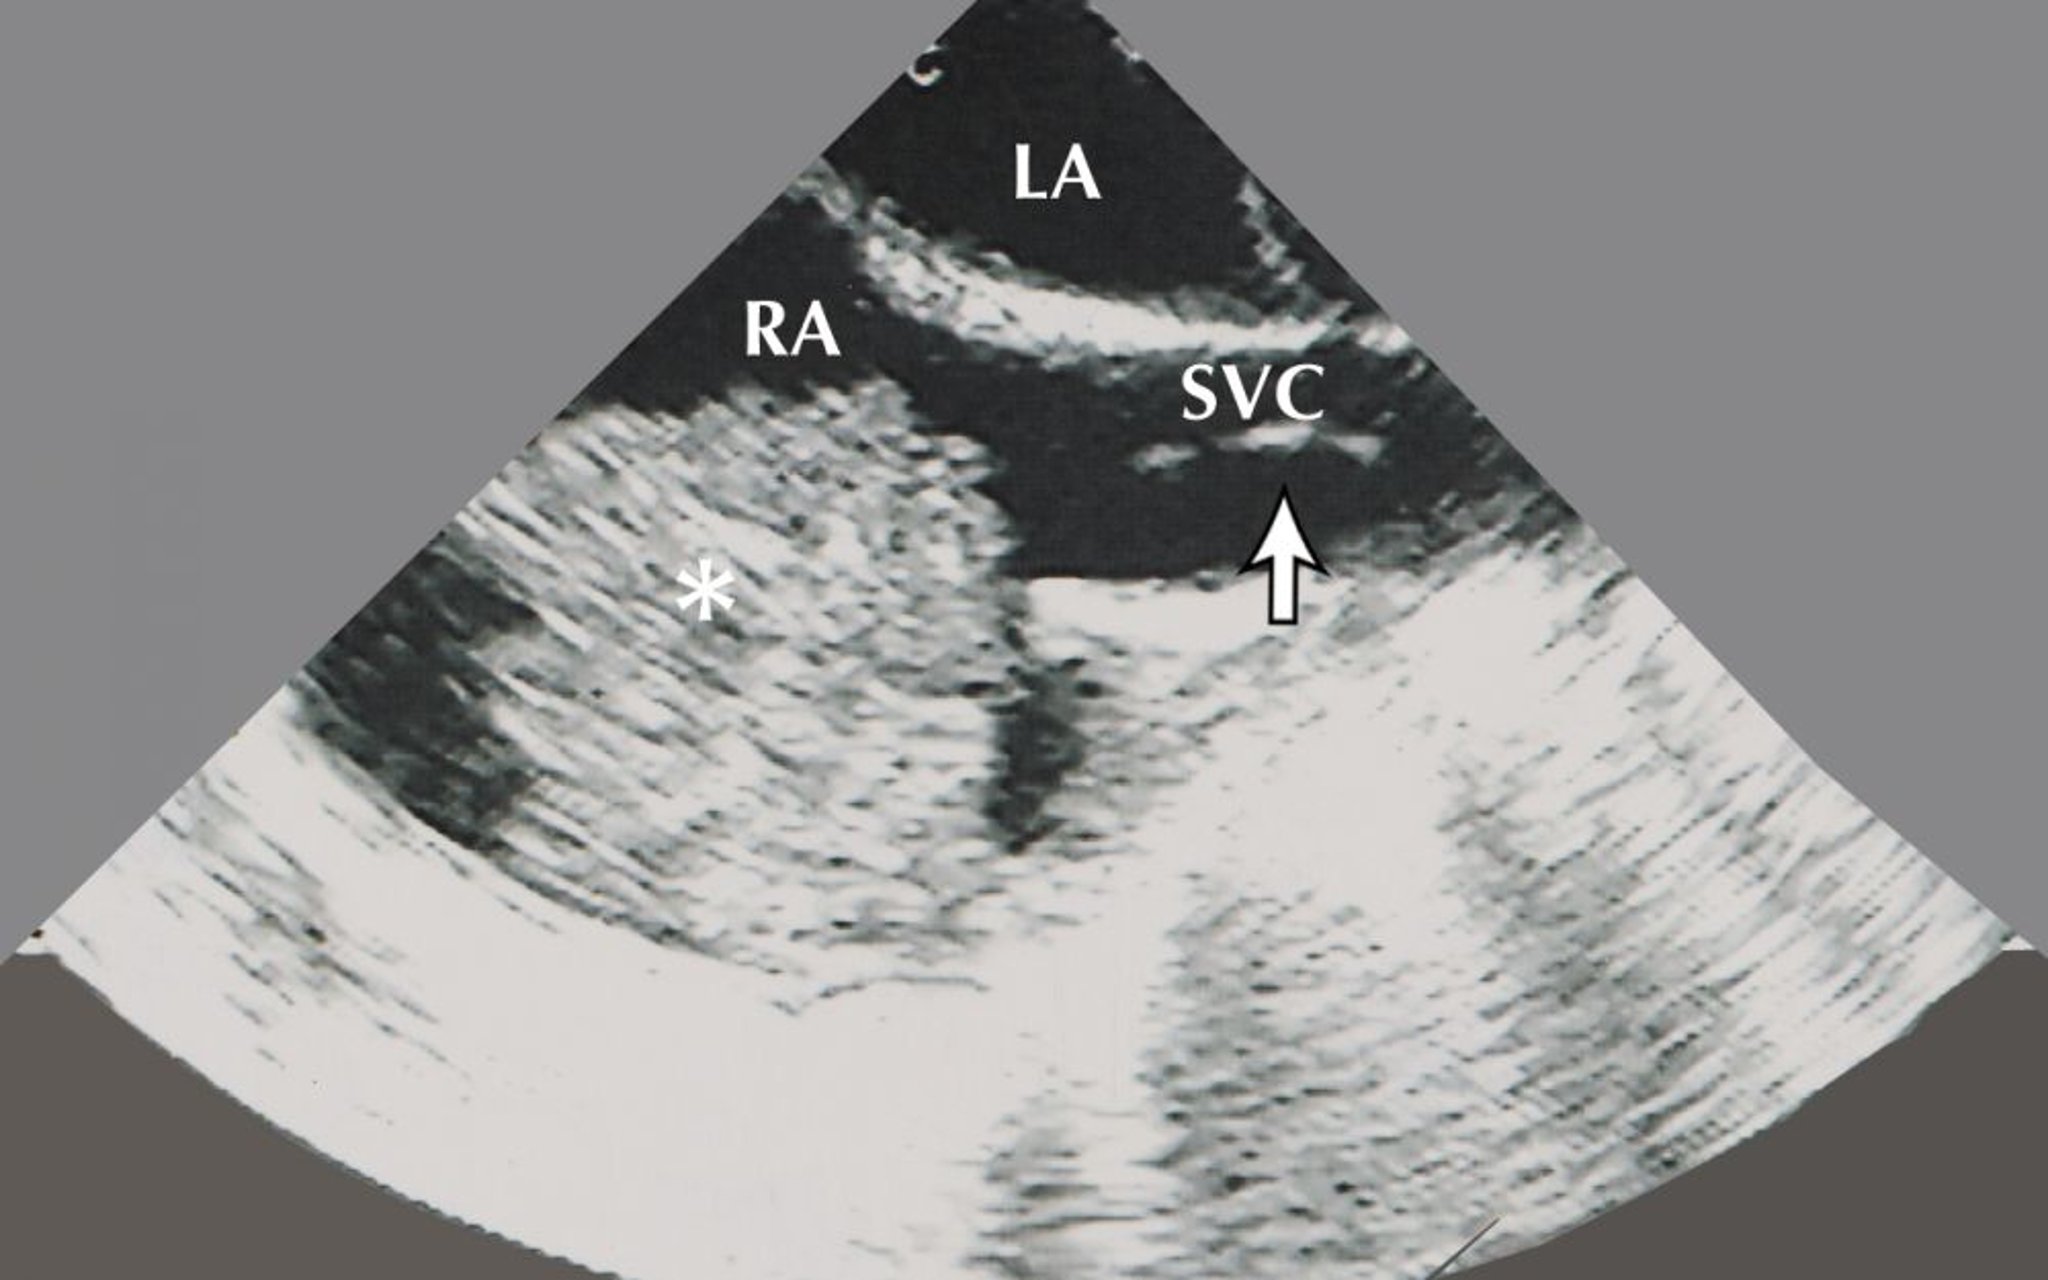

Cette image montre un myxome auriculaire (indiqué par l'astérisque) dans l'oreillette droite. L'oreillette gauche et un bioptome de biopsie (indiqué par la flèche) dans la veine cave supérieure sont également visibles sur cette image échocardiographique.